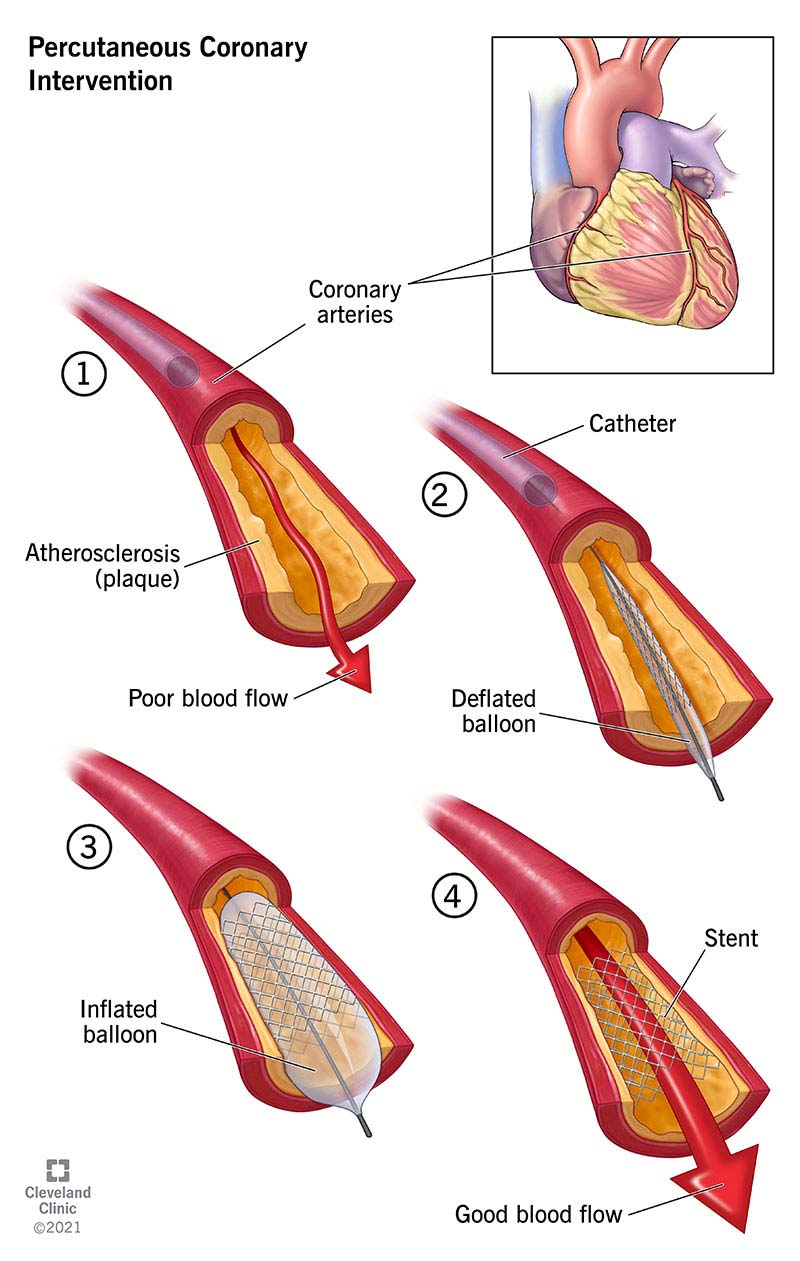

nonsurgical, flow, circulation, structural, balloon

Percutaneous Coronary Intervention (PCI)

-Minimally invasive ___________ procedure performed to improve blood ____ in one or more segments of coronary ___________

-Can be used for evaluation/interventional treatment for ___________ heart disease like adult congenital heart disease or valvular heart disease

-Most commonly used revascularization procedure

-Primarily involves the use of ________ angioplasty + intracoronary stenting

catheter, artery, blockage, widen, increase, stent

Balloon Angioplasty

-A specifically designed _________ is placed in a peripheral ______, and a tiny balloon is guided through the artery to a _________ within coronary circulation

-Balloon is inflated to _____ the opening and _______ blood flow to the heart. Part of PCI

-_____ is often placed during procedure to keep artery open after the balloon is deflated and removed